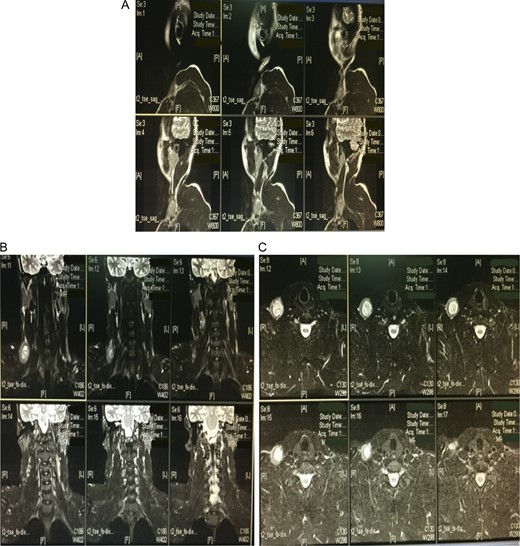

A CT scan exam with contrast was performed, which confirmed the presence of dilatation measuring 31.6 × 42.31 mm on cross section in the internal jugular vein (right side) in the lower part of the neck (Fig. 2A). Magnetic resonance venography (MRV) was ordered, which further confirmed the diagnosis of an aneurysmal dilatation in the right internal jugular vein (Fig. 2 B and C).

A computed tomography scan with contrast showing a dilatation in the internal jugular vein (right side) in the lower part of the neck measuring 31.6 × 42.31 mm on the cross section (A). Magnetic resonance venography further confirmed the diagnosis of an aneurysmal dilatation in the right internal jugular vein (B and C).